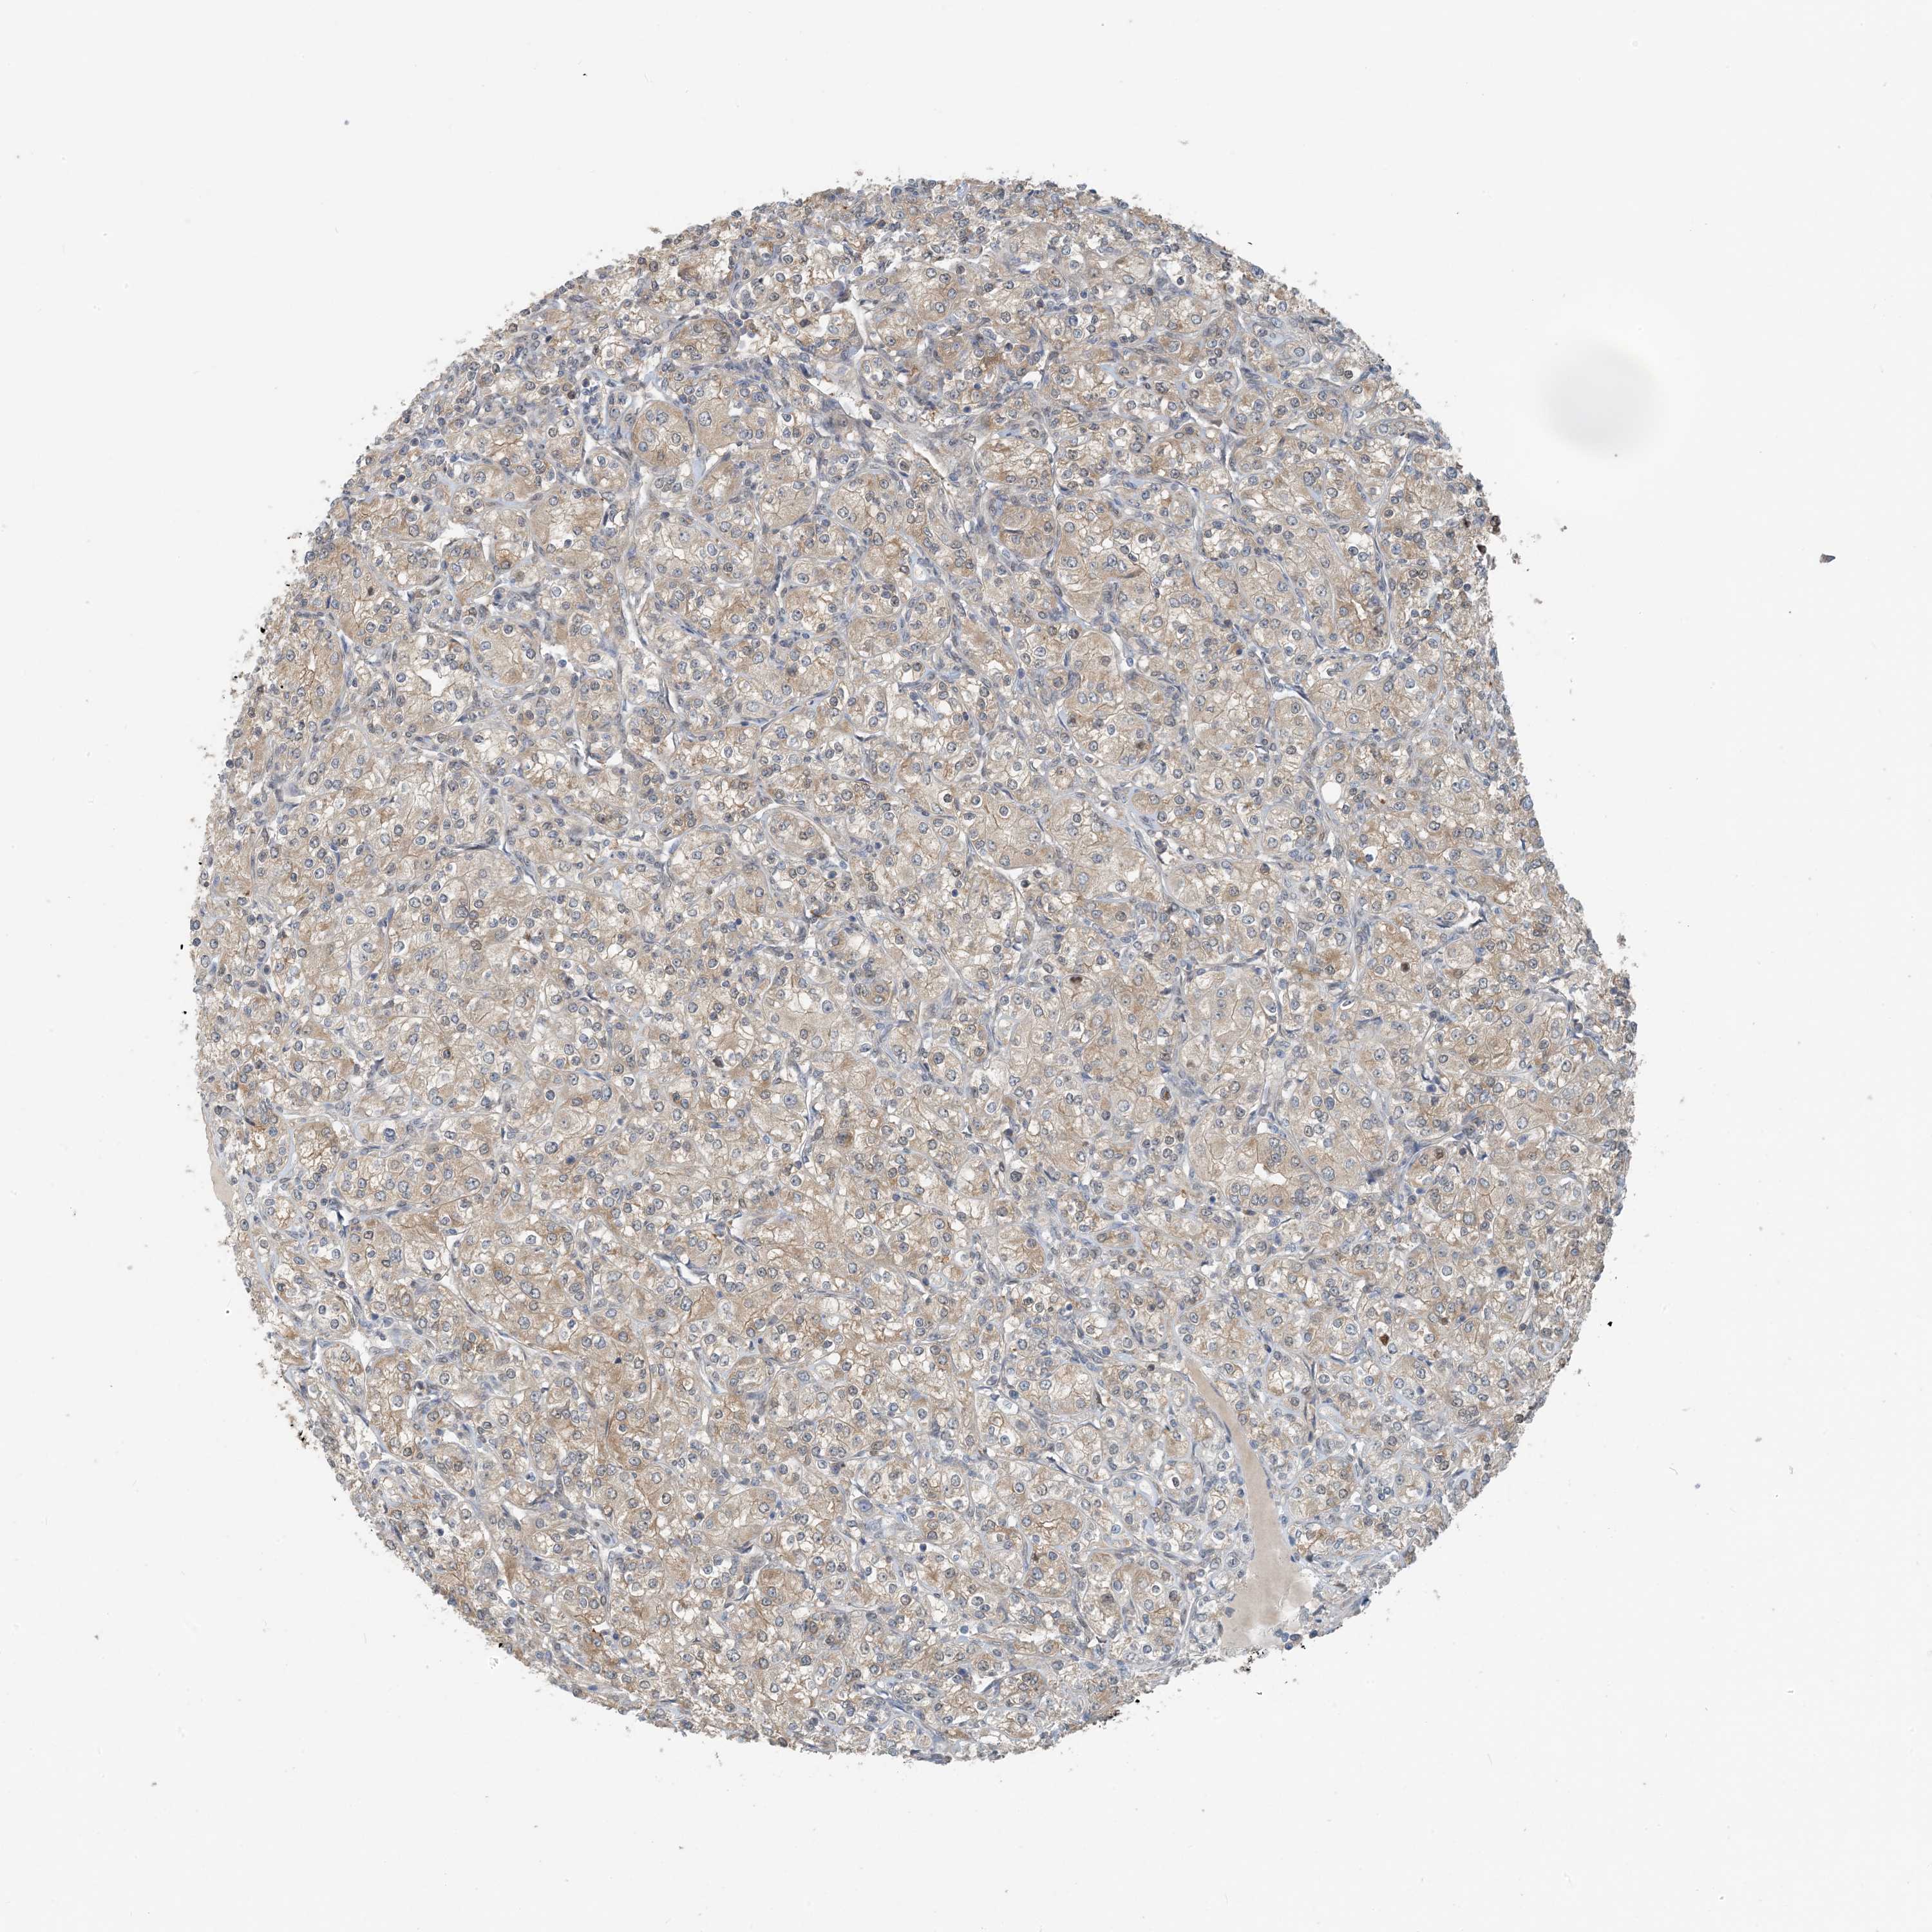

CANCER RENAL CANCER Show tissue menu

Kidney chromophobe

KIDNEY CHROMOPHOBE (TCGA) - Interactive survival scatter ploti

ZC3H12A is not prognostic in Kidney Chromophobe (TCGA)